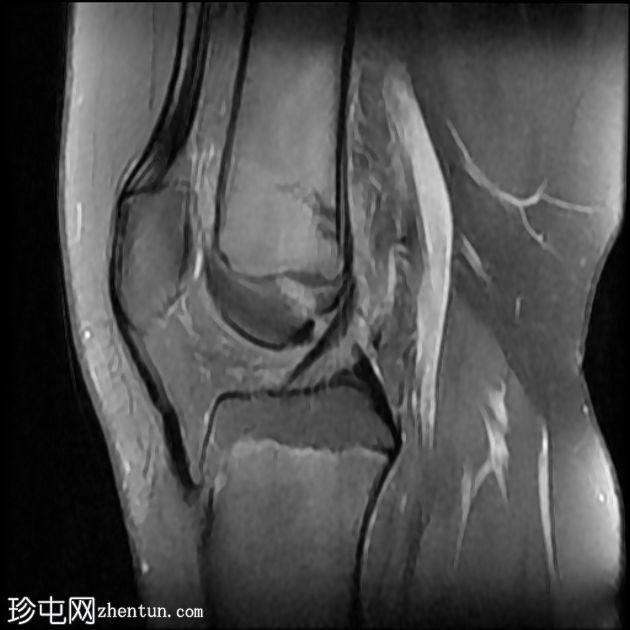

2.jpeg

矢状位

T2

股骨远端干骺端横向应力骨折线,在所有脉冲序列(T1、T2和STIR)上均呈低信号。其周围有骨髓水肿样信号。邻近骨膜软组织呈水肿样信号。

外侧半月板飞边。

髌腱止点增厚,信号增强,内侧有小部分撕裂。伴有胫骨结节突出和不规则,可能提示慢性Osgood-Schlatter病。